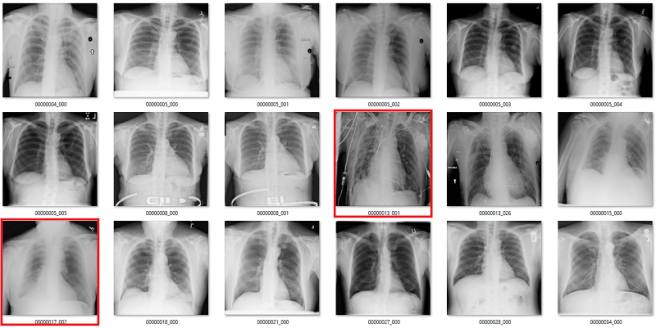

What follows is a bunch of pictures based on the labels in the dataset. In this case, they are pseudo-random. Like I said, it doesn’t have to be perfect. They are randomly chosen sequential sets of 18 images. They are not cherry-picked.

Also, I have tried to err on the side of caution, in the sense that I favour the label class when a case is equivocal.

In all the images, red = clearly wrong label. Orange = I doubt it, I wouldn’t report it, but I can’t really exclude it. Correlate clinically :p

Pneumothorax

A pneumothorax is when there is air in the pleural space around the lung. This can cause the lung to collapse, and is a pretty serious finding. They can be really subtle on x-rays and are often missed.

At first glance, the labels look good. In these 18 cases, only the one highlighted in orange is a bit questionable, and that may just be because I am not looking at the image in diagnostic conditions.

But the green boxes are a problem. These are cases of pneumothorax where the patient has already been treated with a chest drain. There are two issues here:

- This isn’t a medically important problem. We want to avoid missed pneumothoraces, and by definition these have not been missed.

- If so many of the images have chest drains, an AI system will probably learn to identify chest drains instead of pneumothoraces. It is entirely likely that the majority of image batches the model sees will contain no pneumothorax without a chest drain.

Fibrosis

We already saw above that the fibrosis labels are low accuracy, even being generous. But again, the problem is worse. In this image, the reds are incorrect labels, but the orange labels are where I have no idea. There are pleural effusions and/or consolidation. Could there be fibrosis under that? Sure, but there is no way to tell on these pictures.